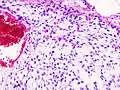

| Histopathologic image of chondrosarcoma of the chest wall. Surgical resection of recurrent mass. H & E stain. | |

Imaging studies – including radiographs ("x-rays"), computerized tomography (CT), and magnetic resonance imaging (MRI) – are often used to make a presumptive diagnosis of chondrosarcoma.[9] However, a definitive diagnosis depends on the identification of malignant cancer cells producing cartilage in a biopsy specimen that has been examined by a pathologist. In a few cases, usually of highly anaplastic tumors, immunohistochemistry (IHC) is required.